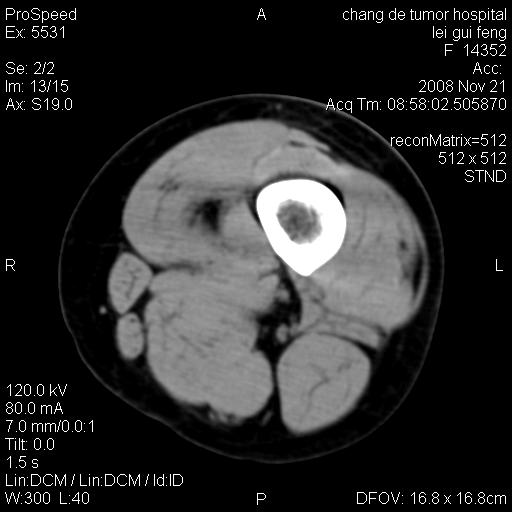

标题: CT16807:女 41 无不适 [打印本页]

标题: CT16807:女 41 无不适

考虑皮样囊肿可能性大

血管瘤可能

血管瘤

血管瘤可能性大!

黏液瘤或表皮杨囊肿

不排除横纹肌肉瘤可能。

血管瘤可能性大或畸胎瘤

考虑脂肪肉瘤

考虑血管瘤可能性大;不排除肉瘤可能。建议行活检。

脂肪肉瘤?

双是软组织肿瘤,病灶内多发钙化,另可见多量脂肪密度影,考虑畸胎瘤,血管瘤,不除外其他